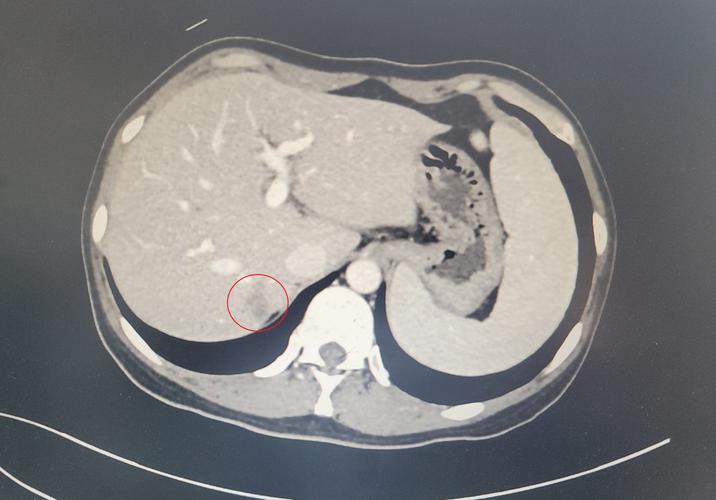

比如结直肠癌,一旦发现结直肠癌,一定要做下肝脏的检查,看看有没有转移,这是常规。因为结直肠癌太容易肝脏转移了。如果有结直肠癌肝脏又有结节,而且不仅一个,基本都是转移了,那么分期就是晚期。像这样的病例,在我工作中,数不胜数。下图就是结肠癌肝转移的图像。